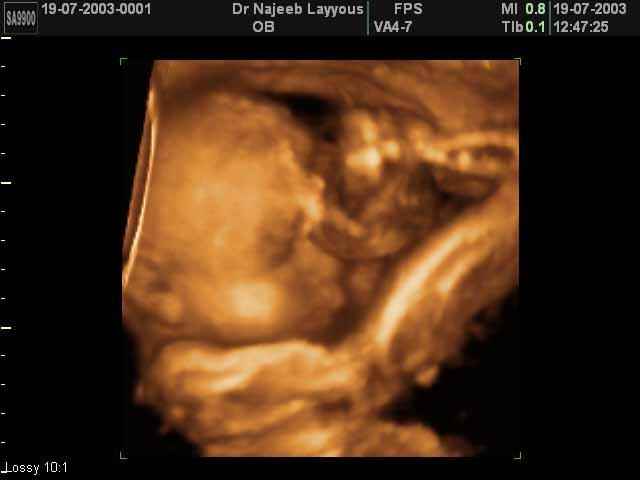

- صور جانبية لرأس الجنين

صور جانبية لرأس الجنين بجهاز الالتراساوند ثلاثي الأبعاد | الدكتور نجيب ليوس